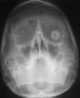

An ocular prosthesis, artificial eye or glass eye is a type of craniofacial prosthesis that replaces an absent natural eye following an enucleation, evisceration, or orbital exenteration. The prosthesis fits over an orbital implant and under the eyelids. [Source: Wikipedia ]